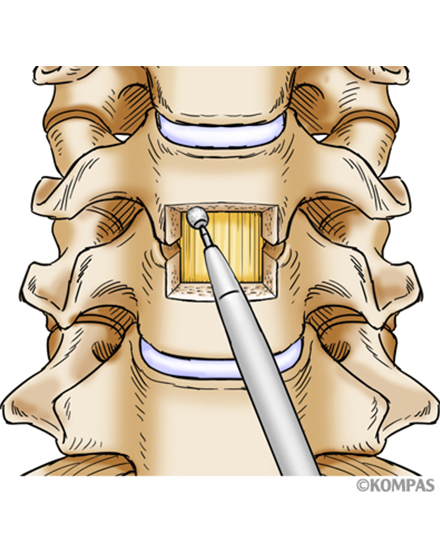

頚椎前方除圧固定術

適応となる疾患:頚椎椎間板ヘルニア、頚椎症性神経根症など

頚部の前方より切開し椎間板や骨の出っ張りを切除し、神経の圧迫を解除します。最近は、椎間板や骨を切除した部分に、椎体間ケージと呼ばれる箱型の金属を使用することで、腰骨からの採骨が不要となり手術時間が短縮できます。また、術後の採骨部痛(骨をとる部分の痛み)を防ぐことができます。手術時間は1時間~1時間30分ぐらいで、翌日から歩行が許可されます。入院期間は通常10~14日間ぐらいになります。